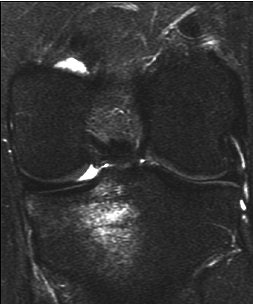

| A 31-year-old man with fast resolution of bone bruise, reticular lesion type. Coronal T2-weighted fast-suppressed images (TR/TE, 12/3,700; fat saturation; section thickness, 3 mm; field-of-view, 180 x 135 mm; matrix, 385 x 224) show fast resolution of bone bruise from baseline (above), to three-week follow-up (middle), and at nine-week follow-up (below). |